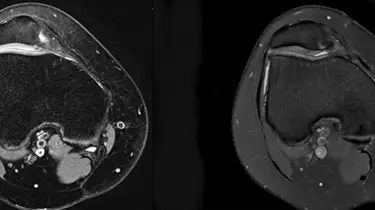

Før et indgreb får du både røntgen og MR-scanning, så kirurgen kan vælge den rette metode til netop dit knæ.